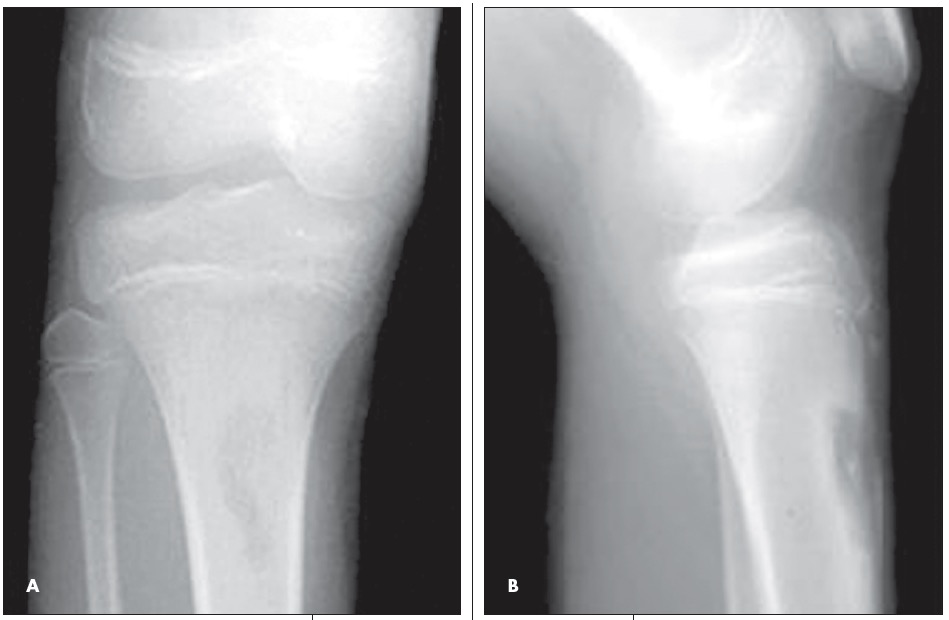

ABSTRACT: Most musculoskeletal infections in children result from hematogenous inoculation. Infections vary greatly in severity and complexity. Sequential determination of the C-reactive protein level may be the most important laboratory test in determining response to treatment. High-quality plain radiographs are essential. Ultrasonography, technetium 99m-diphosphonate scanning, and MRI also are used. In acute osteomyelitis, focal bone pain usually is accompanied by fever or malaise; antibiotic therapy is indicated. Gradual and insidious extremity pain develops in children who have subacute osteomyelitis. Classic features of chronic osteomyelitis include dead bone and reactive new bone; surgery may be needed. Typically, septic arthritis has an acute onset. Treatment includes arthrotomy and joint irrigation.